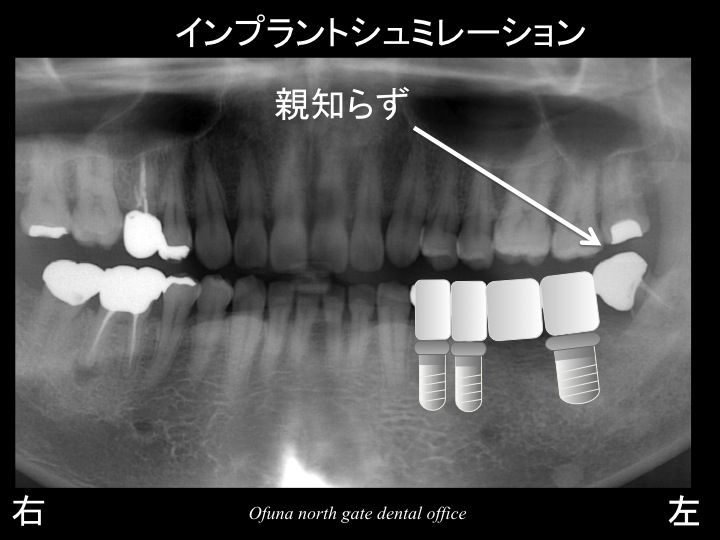

以下が初診時です。

現在の欠損部を見てみましょう!

下顎左側の奥歯が2歯欠損しています。

つまり、歯が2歯分欠損しているために、

3歯の歯を土台として、ブリッジとしてあるのです。

インプラントの治療計画は以下のように考えられます。

一番奥の歯は親知らずですので、

この歯を抜歯した後は、そのままです。

この部位にはインプラントを埋入しません。

以下は、実際にインプラントを埋入した直後です。

抜歯予定の歯は仮歯の土台として使用します。

もちろん、インプラント手術直後から天然歯を土台として仮歯が使用可能ですので、歯がない日は1日もありません。